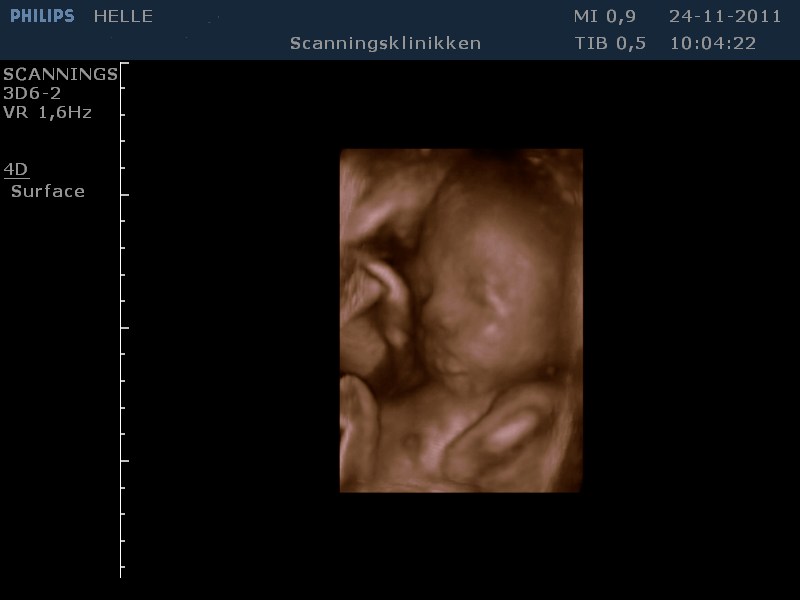

Her går det også godt, - er lige kommet hjem fra en fantastisk 3D scanning. Vores lille pige har det godt og er helt igennem fin! SÅ SØD! Hun har indhentet den manglende vægt og ligger nu lige over gennemsnittet med ca. 1500 g, så det er dejligt!